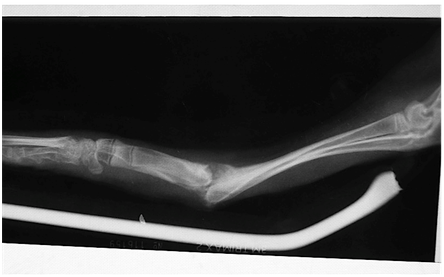

Osteosynthesis was performed by 2.0, 8-hole stainless steel Synthes DCP plate (Synthes 2,0 DCP® plate, Synthes Holding AG, 4500 Solothurn, Switzerland) placed on radius in neutral position with seven cortical 2.0mm Synthes (Synthes cortical 2.0mm screw, Synthes Holding AG, 4500 Solothurn, Switzerland) cortical screws. In the distal bone fragment 3 screws were placed, and 4 in the proximal fragment. One hole was omitted above the fracture line due to small distance of plate holes and huge calus in fracture line (10days old fracture). DCP was placed craniomedially 10mm from carpal joint to avoid negative effects on extensor tendons and radial growth plate. No other fixation was applied to the ulna. Muscles fascia and skin were sutured by polydioxanone 4-0 ( PDS® , Ethicon INC, Somerville 08876-0151 New Jersey, USA) by running suture pattern. Surgery procedure was performed within 45minutes to minimise residence in a hospital environment, which hares generally find stressful.1 Robert-Jones bandage with aluminium splint (aluminijska udlaga, Vetom alfa d.o.o., 10000 Zagreb, Croatia) was placed in order to stabilise fragments in a position additionally. Five days later bandage and splint were removed. Range of motion of both elbow and carpal joint were almost normal. The fracture was assessed as clinically stable in the 5th day postoperatively and the animal was weightbearing on its forelimb.

X-ray examination was performed after the surgery while animal was still anaesthetised. Another x-ray was performed 4weeks post surgery and showed complete healing of the radius with thinner remodelling callus but ulnar fracture line was still present. Bone callus was visible and smaller than in a preoperative x-ray. As a time goes on the primary or temporary callus was gradually replaced by mature lamellar bone, and the excess callus was resorbed. Soft tissue swelling and pain was not observed over fracture site. Palpatory there was no excesive callus present. Plate and screw heads could be palpated through the skin. Range of motion of the carpal joint was the same as on contralateral limb. Pronation and supination were possible and painless. Six weeks post operative x-ray showed that both radius and ulna healed completely Figure 2.

Figure 2 Osteosynthesis of radius with 2.0 Synthes stainless steel plate with 7 cortical 2.0 screws. Five weeks postoperatively fracture line is not visible, angulation is not present. Fused radius and ulna within healed fracture.